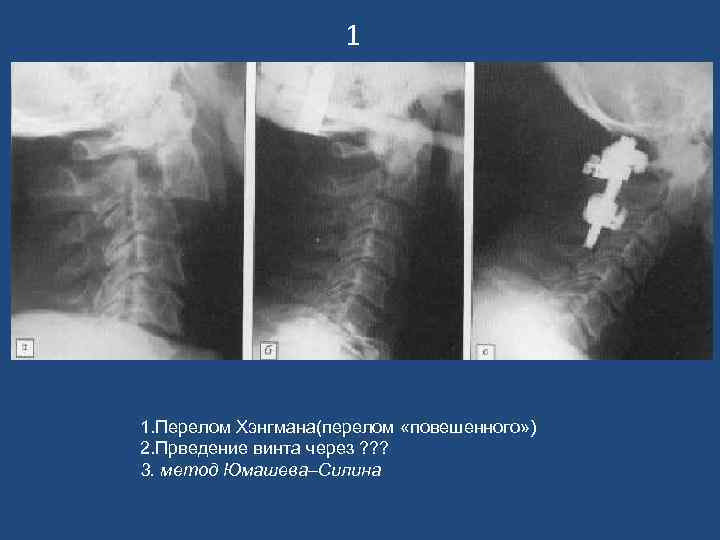

1 1. Перелом Хэнгмана(перелом «повешенного» ) 2. Прведение винта через ? ? ? 3. метод Юмашева–Силина